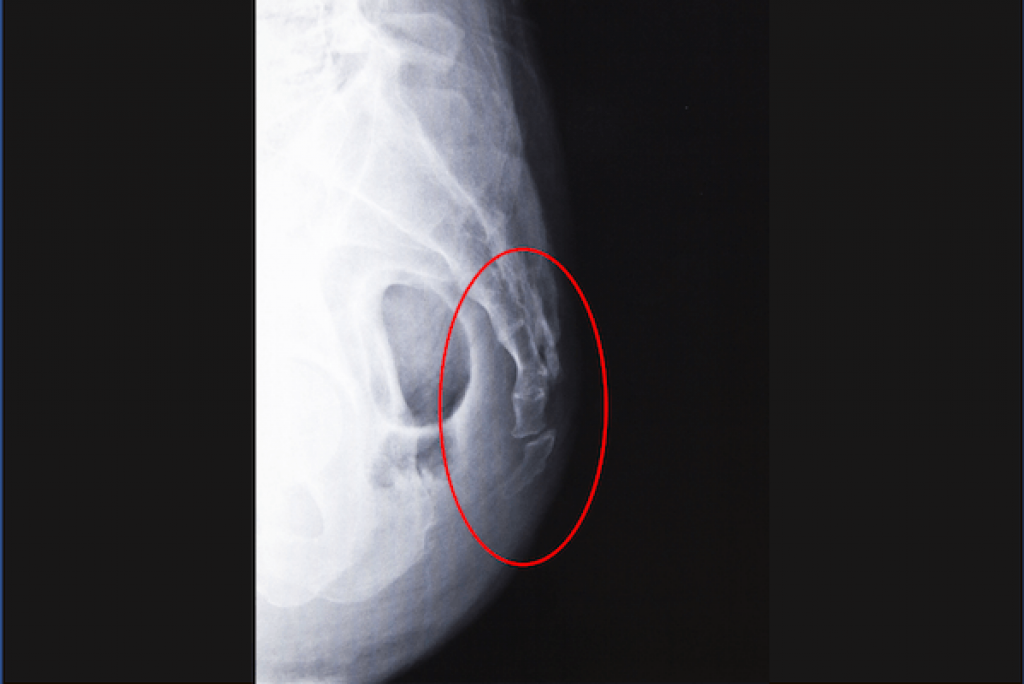

Tailbone injury pictures